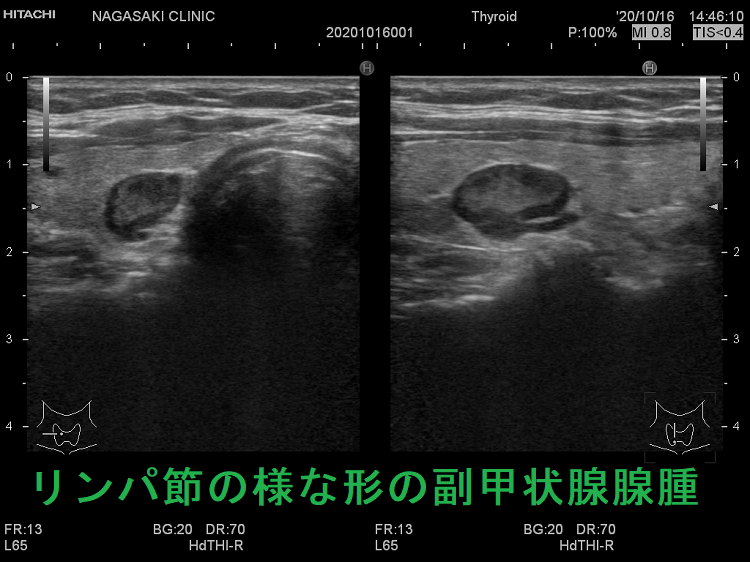

副甲状腺腺腫のように見えるも、実はただのリンパ節

副甲状腺腺腫との違いとして、リンパ節では

- 内部血流が無く

- リンパ門が存在します(ここだけ血流があります)

ケース①②